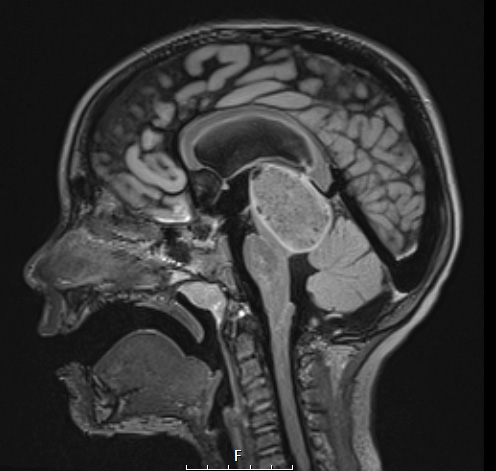

Case 8 History ---- The patient is a 4-year-old male presenting with gait difficulty and papilledema who was found to have ventriculomegaly and a peripherally enhancing tectal mass. Operative procedure: Suboccipital craniotomy for tumor resection. ---- 8A1,2 A large peripherally hyperintense tectal mass is shown in sagittal and coronal views in these FLAIR scans.